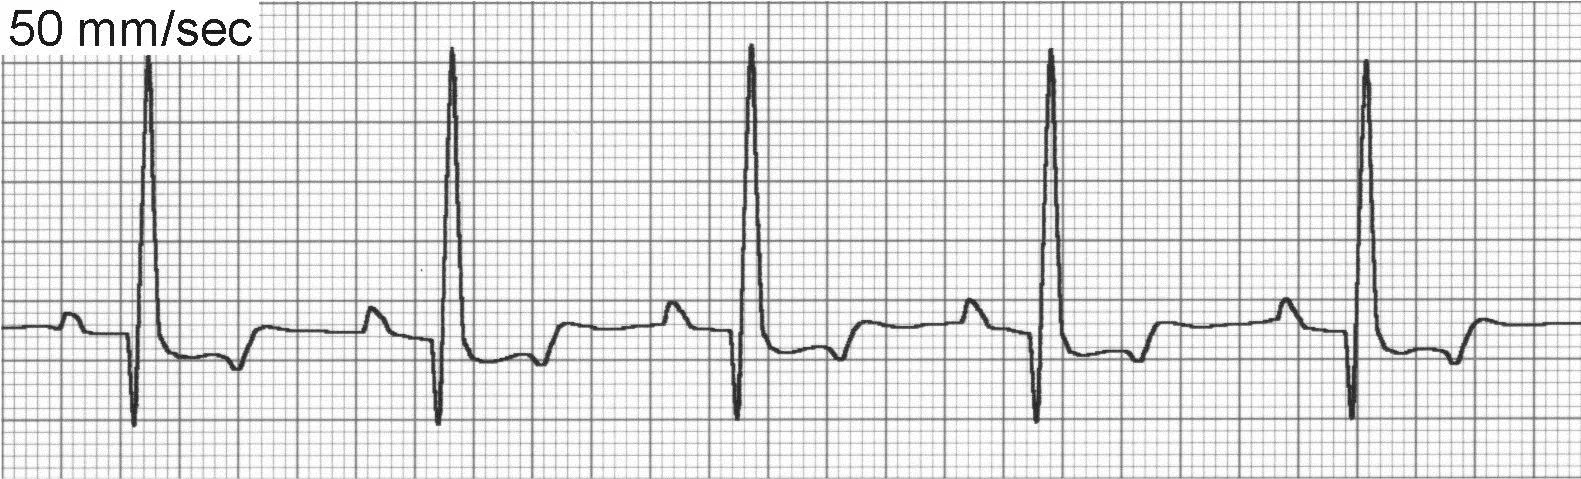

Sinus rhythm (Figure 2) maintains a regular underlying rhythm with P waves present for every QRS complex, QRS complexes present for every P wave, a relatively fixed PR interval, and SV QRS complexes. Sinus rhythm is normal for dogs and cats.

ECG of sinus rhythm